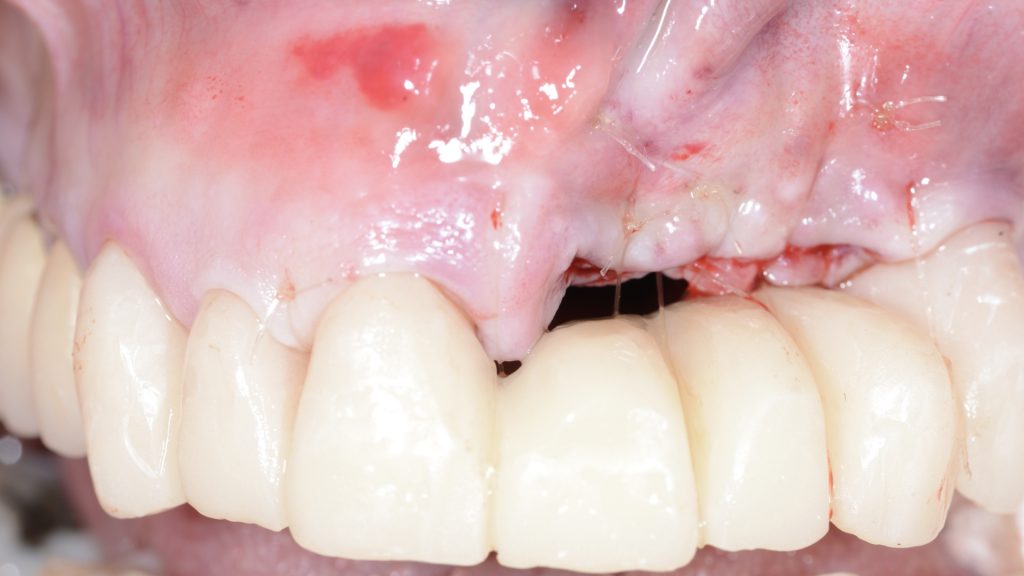

Para no dañar en exceso la zona más crítica, que es la crestal y para conseguir desbridar los defectos periimplantarios y eliminar de forma correcta todo el tejido de granulación se realiza un acceso apical con una incisión a fondo de vestíbulo, tras la eliminación del tejido de granulación se obtiene un injerto de tejido conectivo y se introduce a través de este mismo acceso posicionándolo en la zona crestal para obtener un sellado alveolar compensatorio en la zona de la explantación de los 3 implantes (Figura 4).

Se sutura la incisión realizada a fondo de vestíbulo para obtener un cierre primario mediante sutura reabsorbible y con el uso coadyuvante de un electro-bisturí para minimizar la hemorragia.

Se coloca la prótesis fija provisional dento-soportada desde 13 a 24, sobre los muñones en 13,12,11 y 24 que se habían preparado de forma previa a la intervención y se realizan unos últimos puntos de sutura anclados a la prótesis provisional para traccionar coronalmente. La zona de pónticos de 21, 22 y 23 se liberó para que no contactase con la zona intervenida considerando la inflamación posterior inherente al procedimiento quirúrgico (Figura 5).